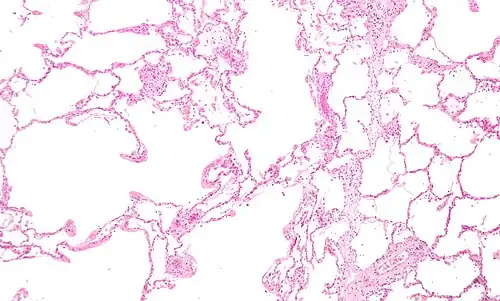

| Micrograph of an emphysematous lung; emphysema is a common respiratory disease, strongly associated with smoking. H&E stain. | |